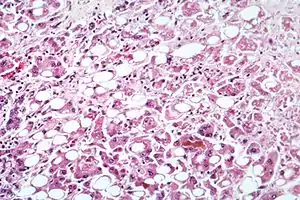

| Alcoholic hepatitis as seen with a microscope, showing fatty changes (white circles), remnants of dead liver cells, and Mallory bodies (twisted-rope shaped inclusions within some liver cells). (H&E stain) | |

Steatohepatitis is seen in both alcoholic and non-alcoholic liver disease and is the culmination of a cascade of events that began with injury. In the case of non-alcoholic steatohepatitis, this cascade is initiated by changes in metabolism associated with obesity, insulin resistance, and lipid dysregulation.[63][64] In alcoholic hepatitis, chronic excess alcohol use is the culprit.[65] Though the inciting event may differ, the progression of events is similar and begins with accumulation of free fatty acids (FFA) and their breakdown products in the liver cells in a process called steatosis.[63][64][65] This initially reversible process overwhelms the hepatocyte's ability to maintain lipid homeostasis leading to a toxic effect as fat molecules accumulate and are broken down in the setting of an oxidative stress response.[63][64][65] Over time, this abnormal lipid deposition triggers the immune system via toll-like receptor 4 (TLR4) resulting in the production of inflammatory cytokines such as TNF that cause liver cell injury and death.[63][64][65] These events mark the transition to steatohepatitis and in the setting of chronic injury, fibrosis eventually develops setting up events that lead to cirrhosis and hepatocellular carcinoma.[63] Microscopically, changes that can be seen include steatosis with large and swollen hepatocytes (ballooning), evidence of cellular injury and cell death (apoptosis, necrosis), evidence of inflammation in particular in zone 3 of the liver, variable degrees of fibrosis and Mallory bodies.[63][66][67]